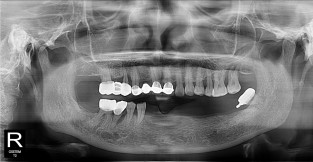

• 2

전체어금니

치료기간 : 2021-11-08 ~ 2022-12-22

1. 상기 x-ray 이미지 모두 동일한 해당 의료기관에서 진료한 환자입니다.

2. 상기 x-ray 이미지 모두 동일 인물의 것입니다.

3. 치료 전 이미지는 2021-11-08에 촬영했으며, 치료 후 이미지는 2022-12-22에 촬영하였습니다.

4. 상기 x-ray 이미지 모두 동일 조건에서 환자분의 동의를 받아촬영되었습니다.

* 임플란트 시술은 환자분의 상태(고혈압, 당뇨 등)에 따라 부작용이 있을 수 있으니, 반드시 전문의와 상담이 필요합니다.

* 임플란트 수술 부작용

: 수술 후 출혈, 교합, 통증, 붓기, 염증 등의 문제점이 발생할 수 있습니다.)